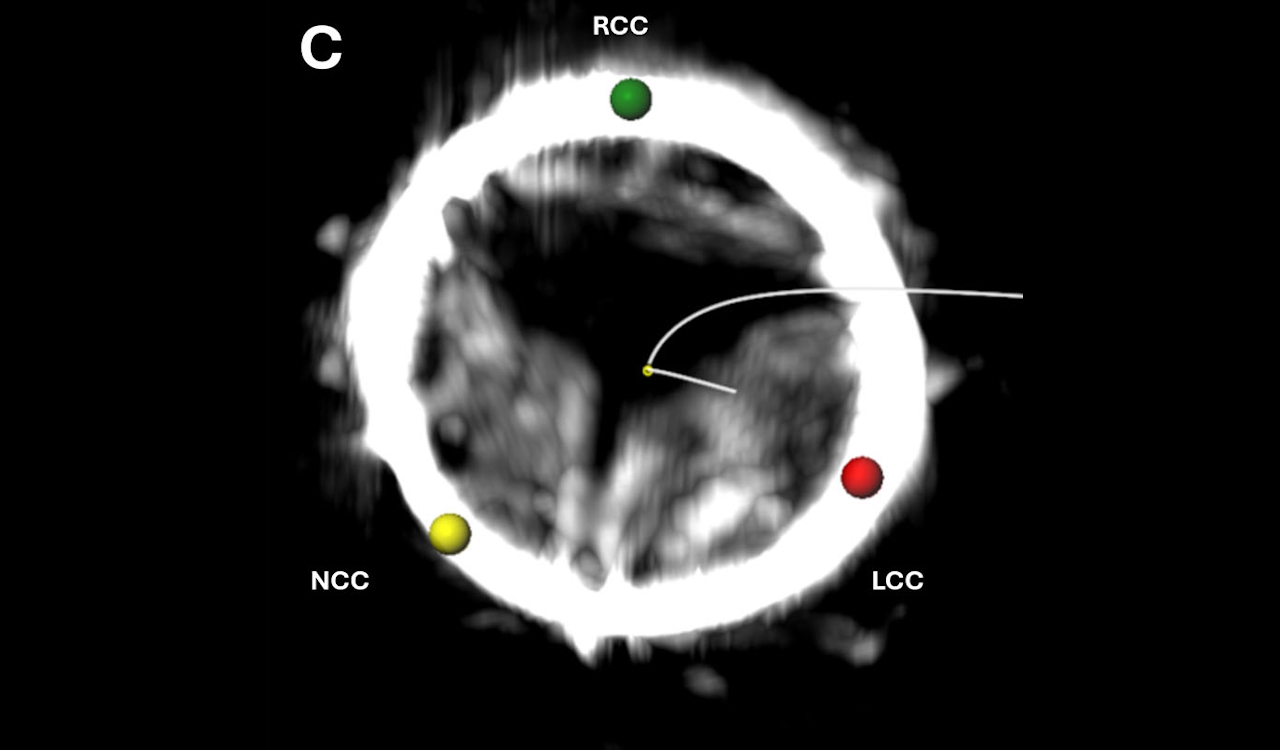

Стулки аортального клапана пацієнта були вкриті щільним кальцифікованим осадом, через що їх не могли відновити. Bruce et al. / Circulation: Cardiovascular Interventions, 2026